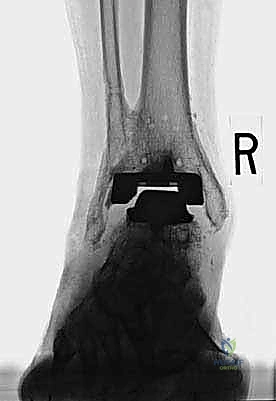

Step 2: Fracture Reduction and Plate Application

"Now, the reduction. Often, the fracture is at the apex of the lateral portion of the prosthesis, making standard lag-screw fixation challenging due to limited bone stock. We'll use a plate here. Assistant, gently reduce the fragments. I'll use a small reduction clamp to hold it. We need to restore the length and rotation of the fibula. Confirm reduction with fluoroscopy. See how it's aligned now? Good. Now, let's grab a small fragment plate, perhaps a 1/3 tubular plate or a specialized lateral malleolar plate. I'm going to pre-bend the plate to hook around the lateral malleolus tip. This contouring is crucial for proper fit and stability. We want it to sit flush against the bone."

TECH FIG 2 • Clinical photograph reveals contouring of plate ( E ) and screw fixation above and below the fracture to maintain stability.

TECH FIG 2 • Intraoperative fluoroscopy demonstrates the fracture location ( C ) and reduction with plate fixation ( D ).

Step 3: Proximal and Distal Screw Fixation

"Once the plate is contoured and reduced, we'll apply it proximally to the fracture first. We need at least three screws traversing the syndesmosis, if possible, to anchor the plate securely to the tibia. These will be cortical screws. Drill, measure, tap, and insert. Ensure these screws are not impinging on the anterior aspect of the tibia or the deep peroneal nerve.

For distal screw fixation, we generally have room for two screws. The first, more proximal screw, should be placed with lag technique if feasible, to achieve interfragmentary compression across the fracture line. This is critical for primary bone healing. The second screw is placed intramedullary, at the very tip of the lateral malleolus, to provide additional stabilization and prevent rotational instability of the distal fragment. Sometimes, a long screw can pass through the plate, into the distal fragment, and then into the medullary canal of the fibula. Again, fluoroscopy is essential to guide every step, ensuring proper screw length and avoiding joint penetration. Let's get a final fluoroscopic view in AP, lateral, and mortise to confirm excellent reduction and hardware placement."